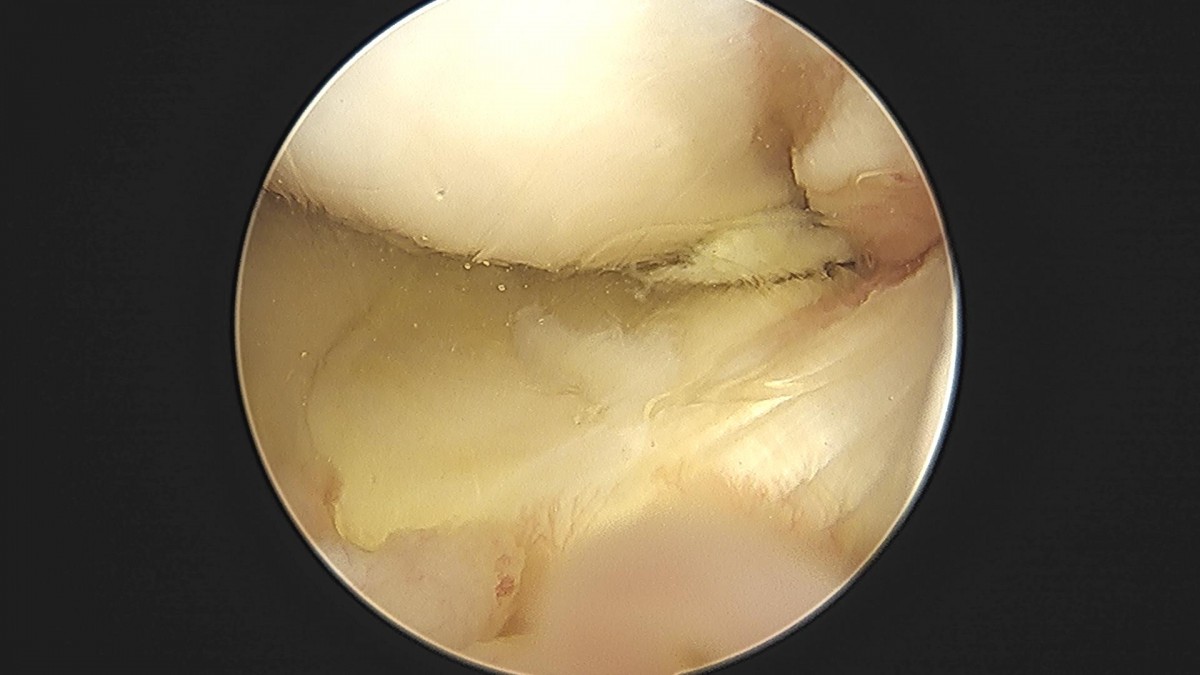

배우한원장님 무릎 반월상연골판 절제술 이관O 환자

ade708f6ffdfd2e6dcf188e7ecb45ff3_1673513853_4727.jpg